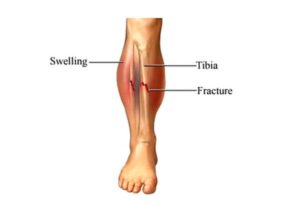

Una fractura ósea es evidente si el hueso sobresale a través de la piel, pero en otros casos, puede ser menos obvio. Los síntomas incluyen dolor intenso, hinchazón, moretones, dificultad para mover o soportar peso en la extremidad, y en algunos casos, deformidad o un ángulo anormal de la extremidad.

Las fracturas óseas pueden variar en gravedad, desde una simple fisura hasta una rotura completa en varias partes. El tipo de fractura influye en las opciones de tratamiento. Las fracturas capilares o por estrés son pequeñas fisuras difíciles de detectar, mientras que las fracturas completas rompen el hueso en dos partes. Las fracturas abiertas implican que el hueso atraviesa la piel, y las fracturas conminutas significan que el hueso se ha fragmentado en múltiples piezas.